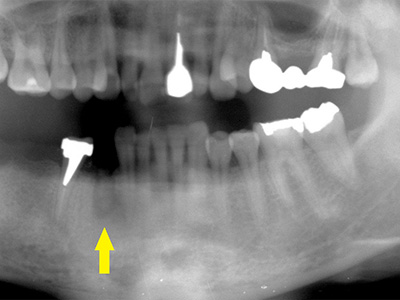

インプラントを埋入するために骨を増やす方法はいくつかありましたが、この場合、患者様ご自身の骨をブロック状で移植するのが最も適していると判断し、自家骨移植術を行ないました。

患者様ご自身の下顎前歯の下方から骨を採取して、骨がなかった部位に移植しスクリューで固定したCT画像です。

黄色矢印部分が、2つの骨片を移植して、固定したところです。 -